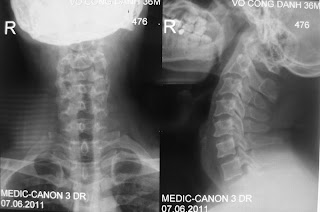

5-6-2011 DH C4-5

A 36 year-old man presened with 2year of neck pain, no  radiated. MRI show central DH C4-5 .